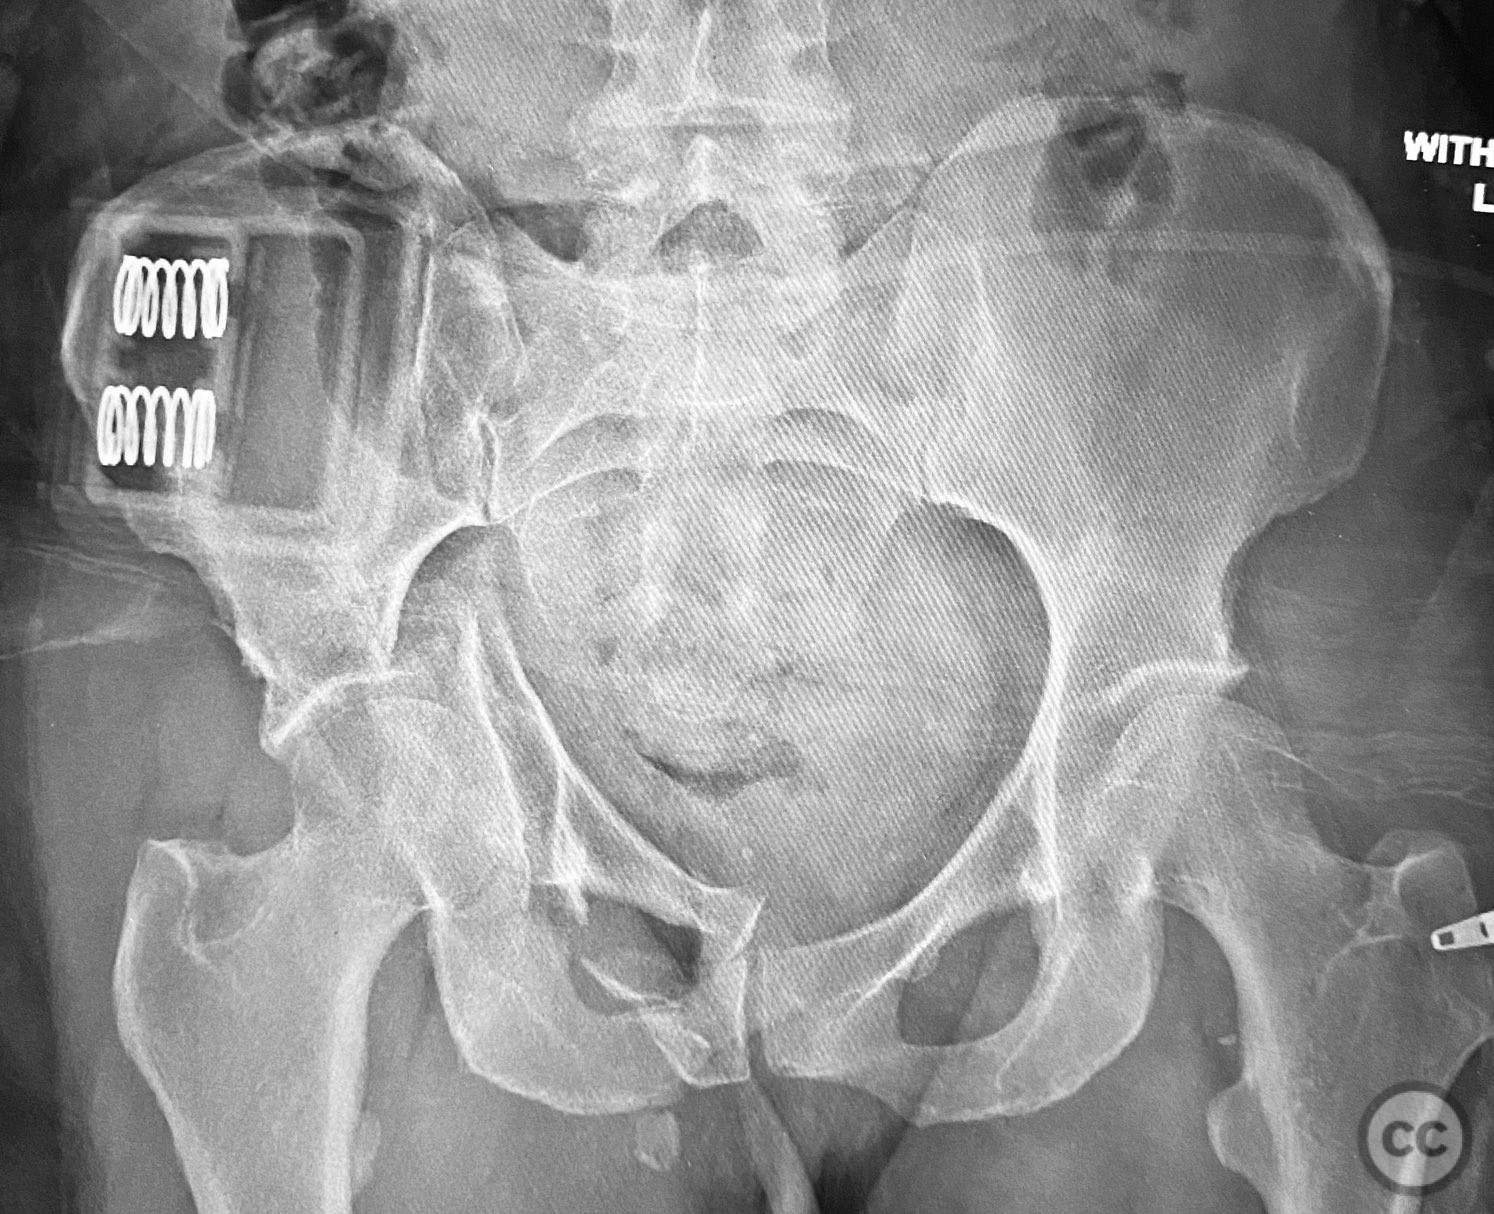

Clinical and radiological findings:  The patient sustained a complex both column acetabular fracture, AO/OTA 62C1, characterized by several large columnar fragments, an independent anterior inferior iliac spine (AIIS) fragment, a notable dome fragment predominantly attached to the posterior wall (PW) fragment, and a distinct parasymphyseal injury zone. Initial application of a pelvic binder resulted in increased displacement of the fracture fragments. Preoperative imaging, including surface renderings and multiplanar CT, demonstrated the independent AIIS fragment, detailed cortical surfaces, and the orientation of fracture planes. The majority of the acetabular dome was associated with the PW fragment, a critical detail for surgical planning and reduction.